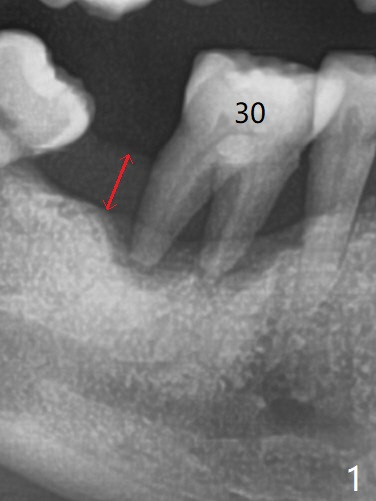

69岁男拔除左上5后右下6疼痛,要求拔除,骨质吸收严重,牙龈厚(图一:双箭头),其实后者是好事,血供好,植牙可以种植浅些(图二),周围放置骨粉(图三:红圆圈)。拍摄根尖片:近中牙槽窝种植与中隔种植,植体长度有优势(图五,四)。